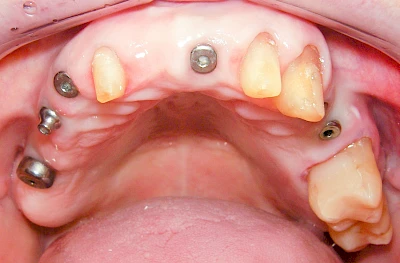

Fehlen einzelne Zähne und die Nachbarzähne sind unbeschadet oder gut zahnärztlich versorgt, werden immer häufiger Implantate gewählt, um die Lücken zu schließen. Auch bei größeren oder verteilten Lücken, wenn keine herausnehmbare Prothese gewünscht ist, werden Implantate für Kronen- bzw. Brückenversorgungen gesetzt. In Einzelfällen entscheiden sich sogar zahnlose Patienten für eine festsitzende Versorgung auf Implantaten.

Varianten zur Verankerung von festsitzendem Zahnersatz auf Implantaten